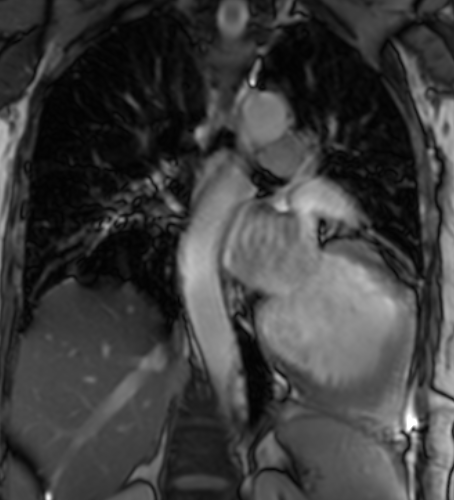

One month later the patient underwent cardiac MR imaging which showed the typical signs of pericardial agenesis: extreme levocardia of the heart resulting in elongation and ectasia of the aorta and pulmonary artery, interposition of lung tissue between the diaphragm and the base of the heart and increased cardiac mobility (‘swinging heart’). The late enhancement (LGE) revealed transmural scarring and hypo- and akinesia of the anterior wall.

Fig 1: MRI: levoposition of the cardiac silhouette, prominent pulmonary artery, and lung tissue between the diaphragm and inferior border of the heart